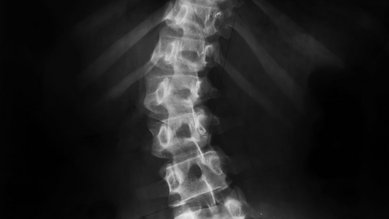

Ergenlikte skolyoz

Ergenlikte skolyoz, omurganın eğrilmesine neden olur. Nedeni bilinmemektedir. Eğrilik devam ederse, düzenli olarak kontrol edilmelidir.

Omur kırığı

Omur kırıklarının çoğu kemik erimesi (osteoporoz) sonucunda meydana gelir. Trafik ve spor kazaları daha nadir karşılaşılan nedenlerdir. Tedavi yaralanmanın şiddetine göre uygulanır.